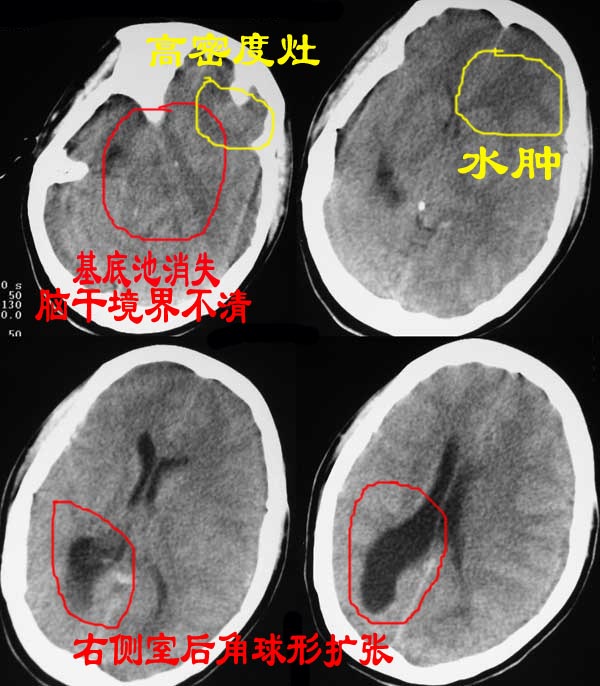

女30y打架前有癫痫发作病史,7天后ct检查如以下图,病人不久后死亡。不解。此人已法医尸解。

从ct图像上我们可以看出以下几个问题,如图示:

从病史中我们还得知:

1、病人受外伤前就有癫痫发作;

2、不知为什么病人在打架后的第七天才作ct检查?

3、病人死亡;

分析:

1、为什么病人在受伤的第七天才作颅脑ct,是因为临床没有神经系统体征///打架时头部没有受外伤///还是其它什么原因?

2、病人在打架前就有癫痫发作,病史有多长///有没有继往病史///还是其它?

3、颅底层面太少,不好猜;

单从现有的ct来看,病人死因不好直接定在脑损伤,因为病史太少,也没有更详细的临床资料;

左额叶大片低密度水肿影,左侧脑室受压,中线右移,打架前有癫痫史,考虑有脑肿瘤,期待结果.

此病人病人在受伤后在家无人管.故七天后病情严重后才到医院的.我见到病人时是在法医办公室的尸体检验报告单.病理结果是脑胶质瘤.